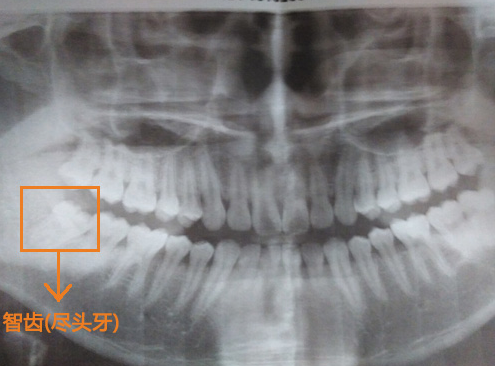

深圳愛康健口腔醫院醫生介紹,長智齒了牙齦腫痛的情況很常見,目前大家采用的方法就是采用冰塊敷臉以及吃一些消炎藥消炎止痛,等到消炎症狀退了以後,很多人就忘記了,但是到醫院檢查一下智齒的情況才是治療牙齦繼續發炎腫痛的關(guan) 鍵。檢查一下智齒的萌出情況,以及找專(zhuan) 業(ye) 醫生判斷時否需要拔除。

還是先到醫院拍片檢查一下自身的智齒情況後,請專(zhuan) 業(ye) 的醫生進行判斷。但是需要提醒各位的是,一般智齒引起牙齦腫痛的時候是不能馬上進行拔牙的,所以到醫院後隻能先消炎,等到炎症好轉以後才能拔牙,這是因為(wei) 有炎症進行拔牙容易感染。所以也不要錯怪醫生為(wei) 什麽(me) 不能在智齒痛得厲害的時候為(wei) 您拔牙了。